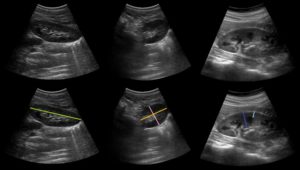

Как проводится УЗИ почек? Существует определенный порядок, разработана методика проведения исследования для получения наиболее точной информации. Техника УЗИ у женщин, не отличается от таковой у мужчин.

Пациент при процедуре находится в нескольких положениях: горизонтально – на спине и на боку, вертикально и сидя. На предварительно освобожденную от одежды кожу наносится специальный гель для улучшения распространения ультразвуковых волн.

Затем с помощью плавного перемещения датчика врач изучает параметры почечной паренхимы и чашечно-лоханочной системы.

По имеющимся временным нормативам почки исследуются в течение 20-60 минут в зависимости от метода, какой применяется (трехмерный или внутриполостной), на допплерографию специалисту дают в среднем 40 минут.

Что определяет врач, проводя УЗИ-диагностику почек?

В процессе исследования врач определяет:

- расположение почек;

- форму и контуры почек;

- размеры почек;

- структуру паренхимы;

- кровоток почек;

- патологические образования, такие как камни, опухоли, кисты, песок.